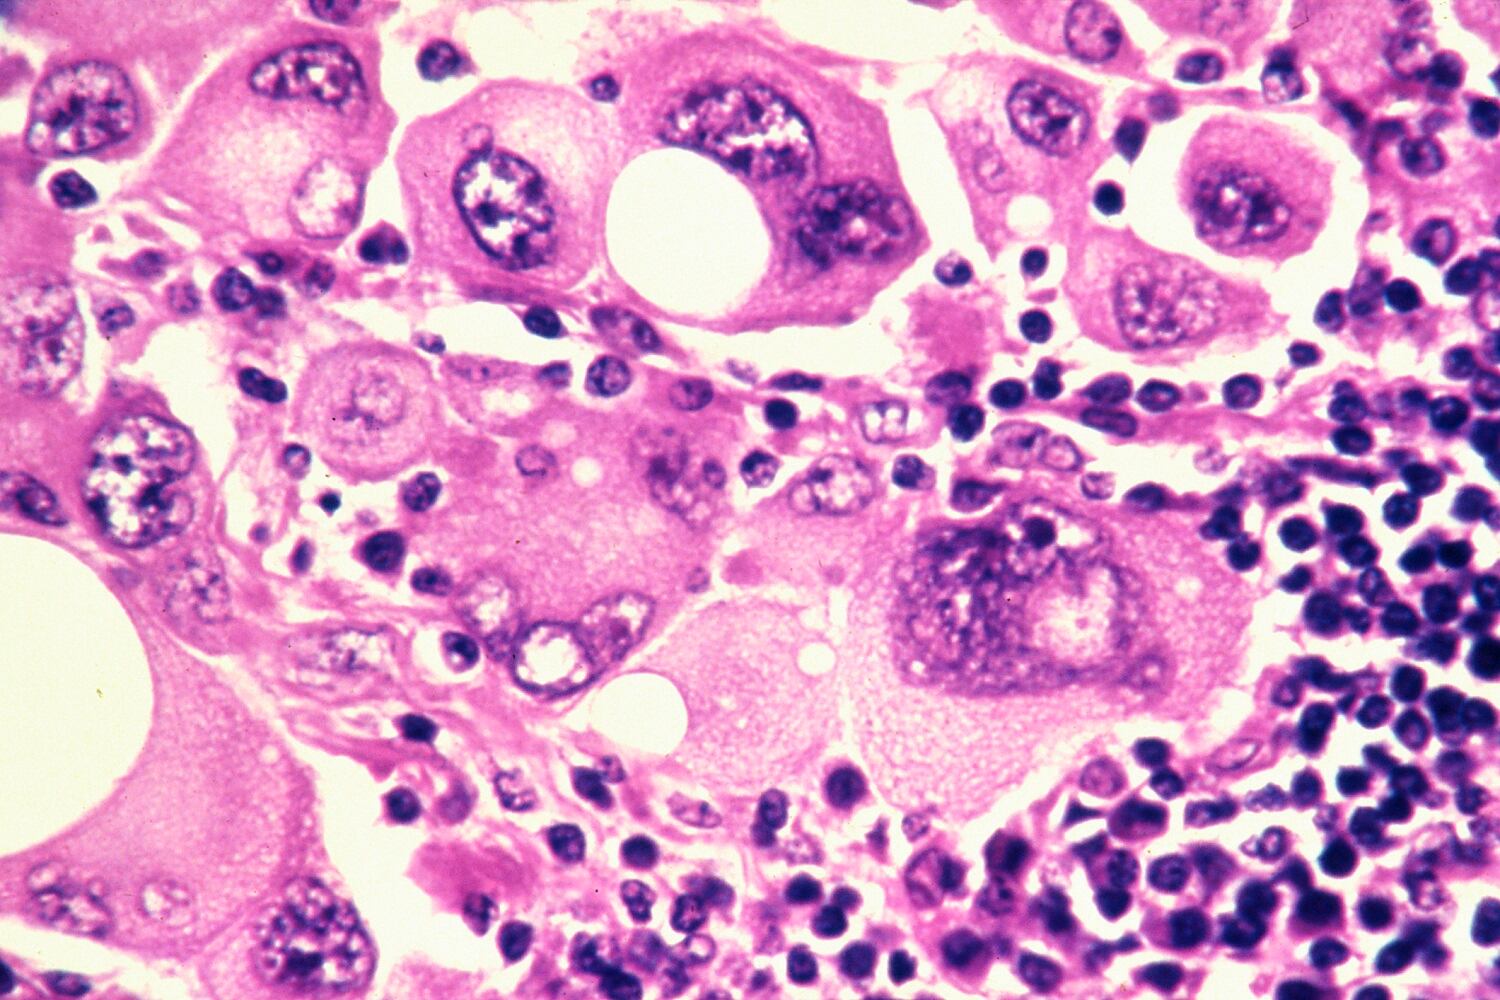

El cáncer de pulmón es una enfermedad que surge por el crecimiento maligno de células del tracto respiratorio, particularmente en el tejido pulmonar. Esta patología es la primera causa de mortalidad por cáncer en los hombres y la tercera, después de colon y mama, en las mujeres. Se estima que 2′206.000 personas fueron diagnosticadas con cáncer de pulmón en 2020.